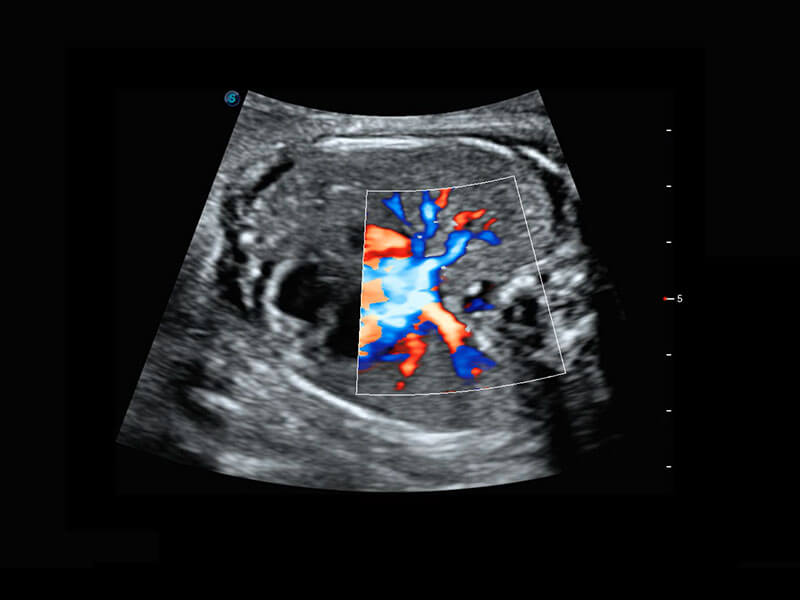

P60搭载宽频带线阵探头、宽景成像、弹性成像技术,为您提供乳腺应用方案。P60支持高频相控阵探头、线阵探头、腹部高频探头、腹部微凸探头等,丰富的探头群搭载敏感的彩色血流成像,适用于新生儿多种脏器检测要求,满足新生儿筛查需求。

乳腺导管癌

乳腺癌显微血流

新生儿肝血管癌